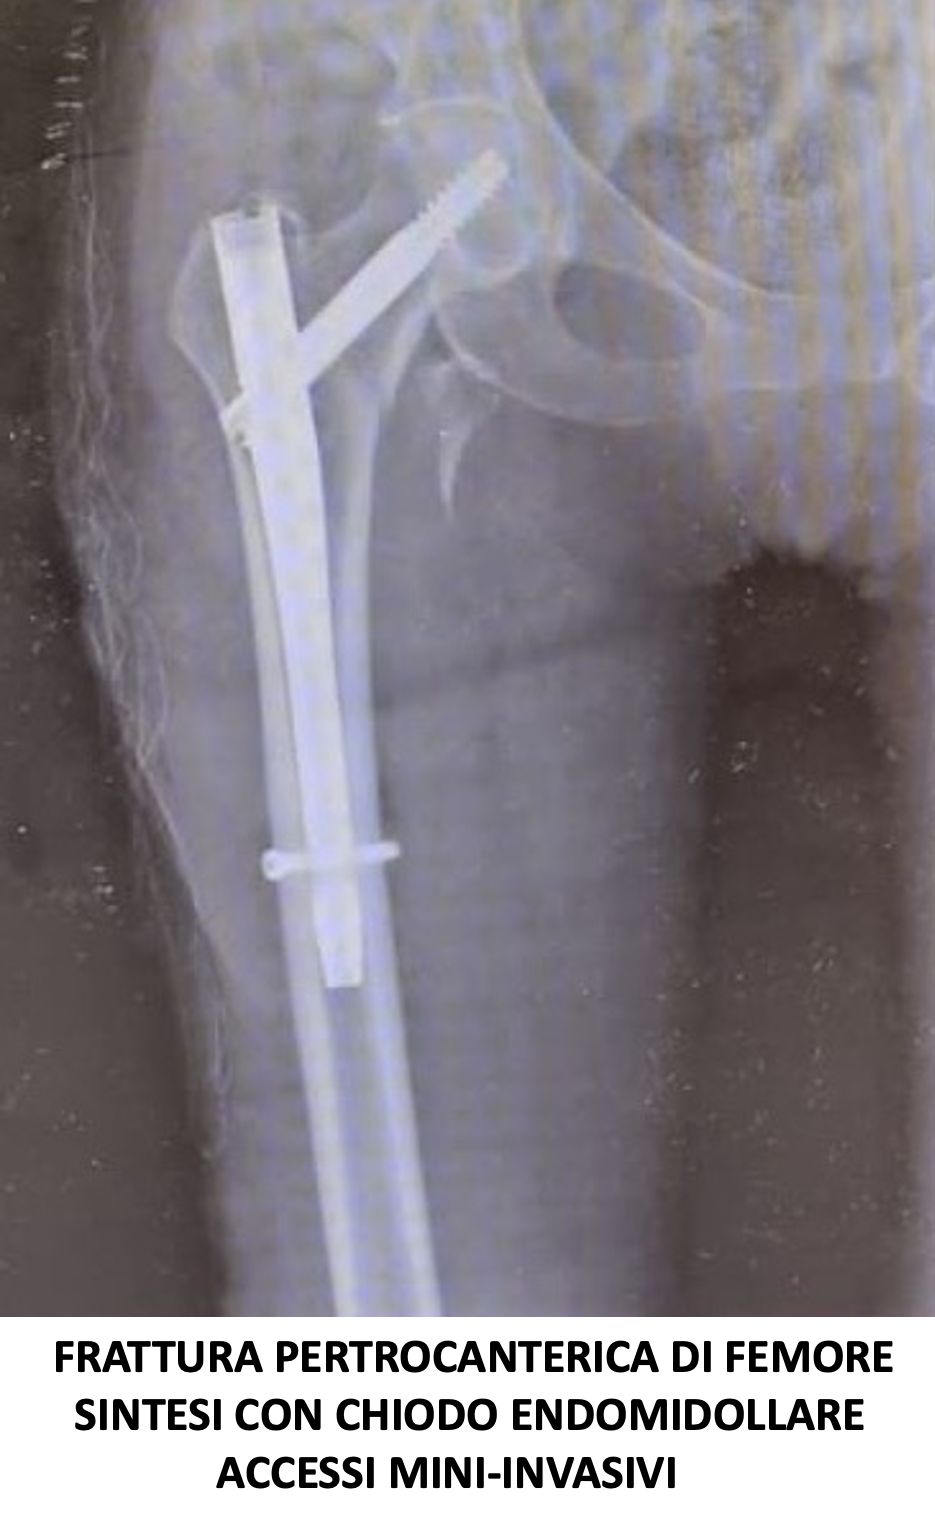

Svolge la sua attività presso l’Ospedale del Mare, occupandosi di chirurgia traumatologica, con predilezione alla protesica di ginocchio e medicina rigenerativa della cartilagine articolare.

• Ortopedia e traumatologia del sistema motorio